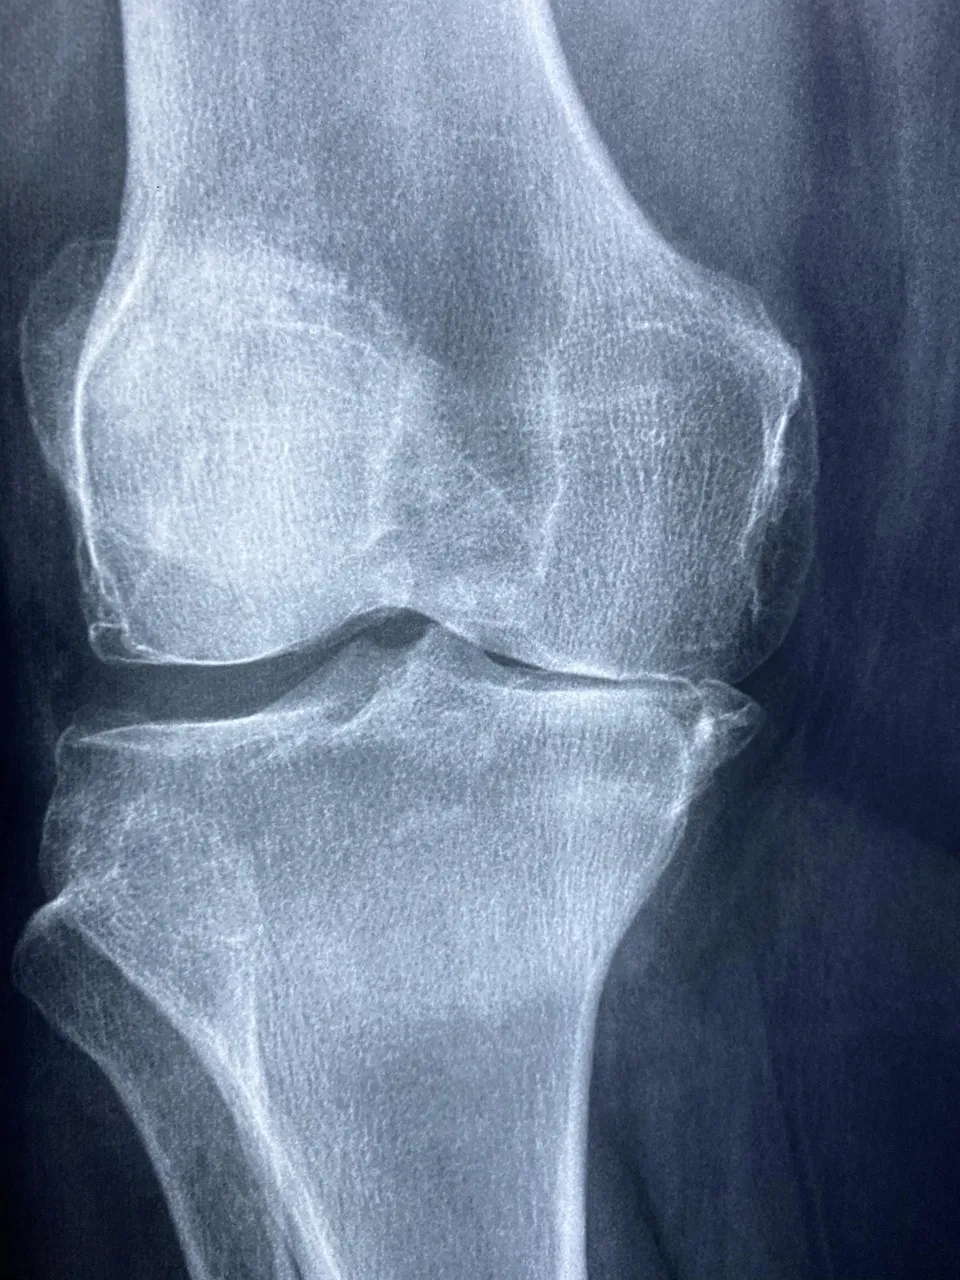

부모님이 느낀 첫번째 콘드로이친 효능 – 무릎 통증 완화

부모님이 콘드로이친을 드시기 전에는 아침에 일어날 때 특히 무릎이 시큰거려 힘들다고 하셨습니다.

한 달 정도 꾸준히 복용하신 후 “요즘은 무릎이 덜 시큰거린다”는 말씀을 하셨어요.

콘드로이친 효능 중 하나가 바로 관절 내 염증을 줄이고 통증 완화에 도움을 주는 것이라고 합니다.

콘드로이친 효능 3 – 관절 윤활 및 유연성 개선

콘드로이친은 관절 속의 윤활 작용을 촉진해 마찰을 줄여주는 역할을 합니다.

부모님이 평소에 계단 오르내릴 때 덜 불편하다고 하셨는데

이 부분도 콘드로이친 효능 중 하나로 볼 수 있겠죠.

실제로 콘드로이친은 관절액의 점도를 높여 유연성을 개선하는 효과가 있다고 합니다.